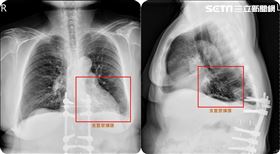

台中婦咳5年胸悶暴瘦 肺部驚見爆漿香腸

台中一名63歲謝姓婦人,近5年一直都有慢性咳嗽病史,...